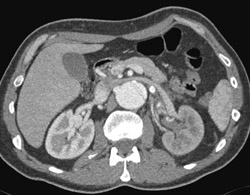

Diagnosis

Normal Vertebral Artery